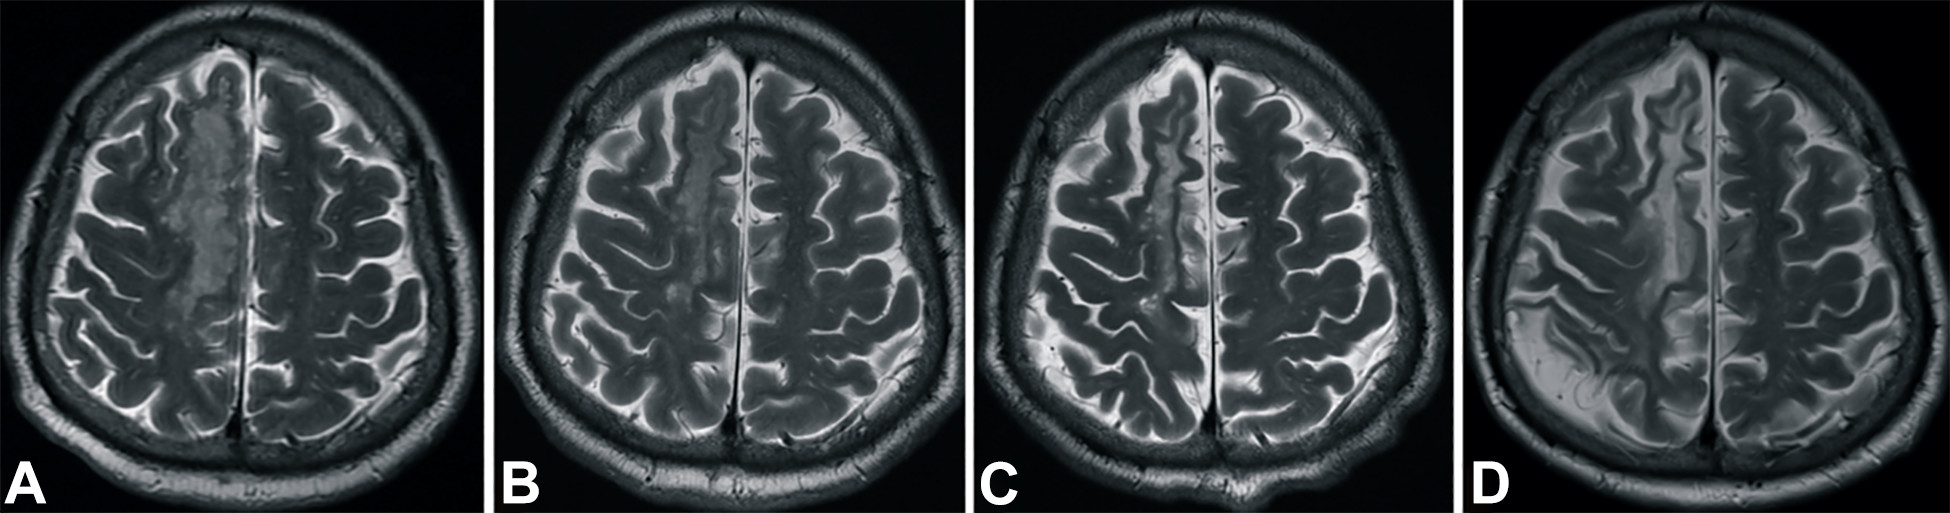

梗塞發生后2小時、8 天、3 個月和 6個月獲得的T2加權圖像顯示右側放射冠白色強度增加(圖3A-D)。

中風后2小時和輸血后6個月獲得的T2加權圖像。

圖3.中風后2小時和輸血后6個月獲得的T2加權圖像。(A)中風后2小時,(B) 輸血后1天,(C) 輸血后3個月,(D) 輸血后6個月